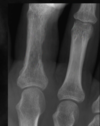

What is seen here in regards to density?

Sclerotic